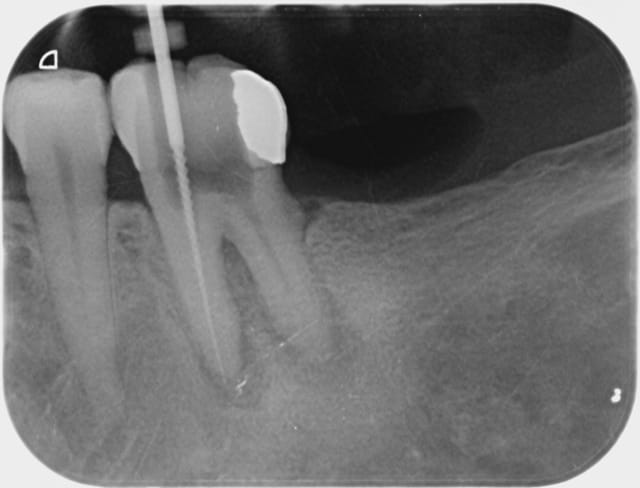

Pas plus tard que ce matin 11 h 30. Patient refoulé d'une premier cabinet, pour une bio sur une 8, qui le prenait en charge habituellement car la collègue n'arrivait pas à accéder à la 8. Envoyé à la fac dentaire, proposition d'intervention sous anesthésie générale ... Patient guère motivé qui échoue chez moi.

2 aiguilles plus tard ... radio curetage de la cavité ... "sans sushi" !

Je vous tiendrais au courant pour la pose de la digue.

18/04/2012 à 20h03

Oulala...une endo sans digue ? Sur nonol ?

Alapex fatou 000 viafkj - Eugenol

Alapex fatou 001 hxrlfs - Eugenol

Alapex fatou 002 onq044 - Eugenol

Je vais t'aider : à supposer que tu aies fait ces radios sur une personne vivante et pas un crâne, je trouve complètement fou que tu préfères t'emmerder à faire des radios limes en place et pas mettre la digue, plutôt que mettre la digue et utiliser un localisateur d'apex qui t'évite de prendre des radios.

Maintenant, si c'est un clamp invisible, je trouve tout aussi inutile de prendre une radio, même avec la digue quand on peut utiliser un localisateur d'apex.